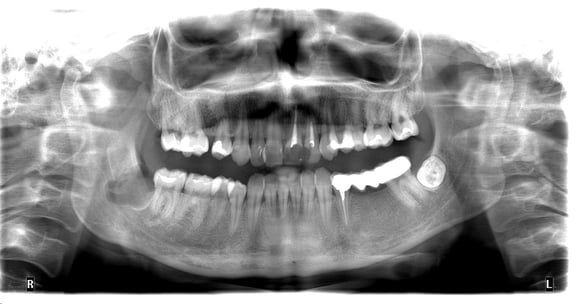

Дистопія зуба мудрості

ОПГ перед операцією